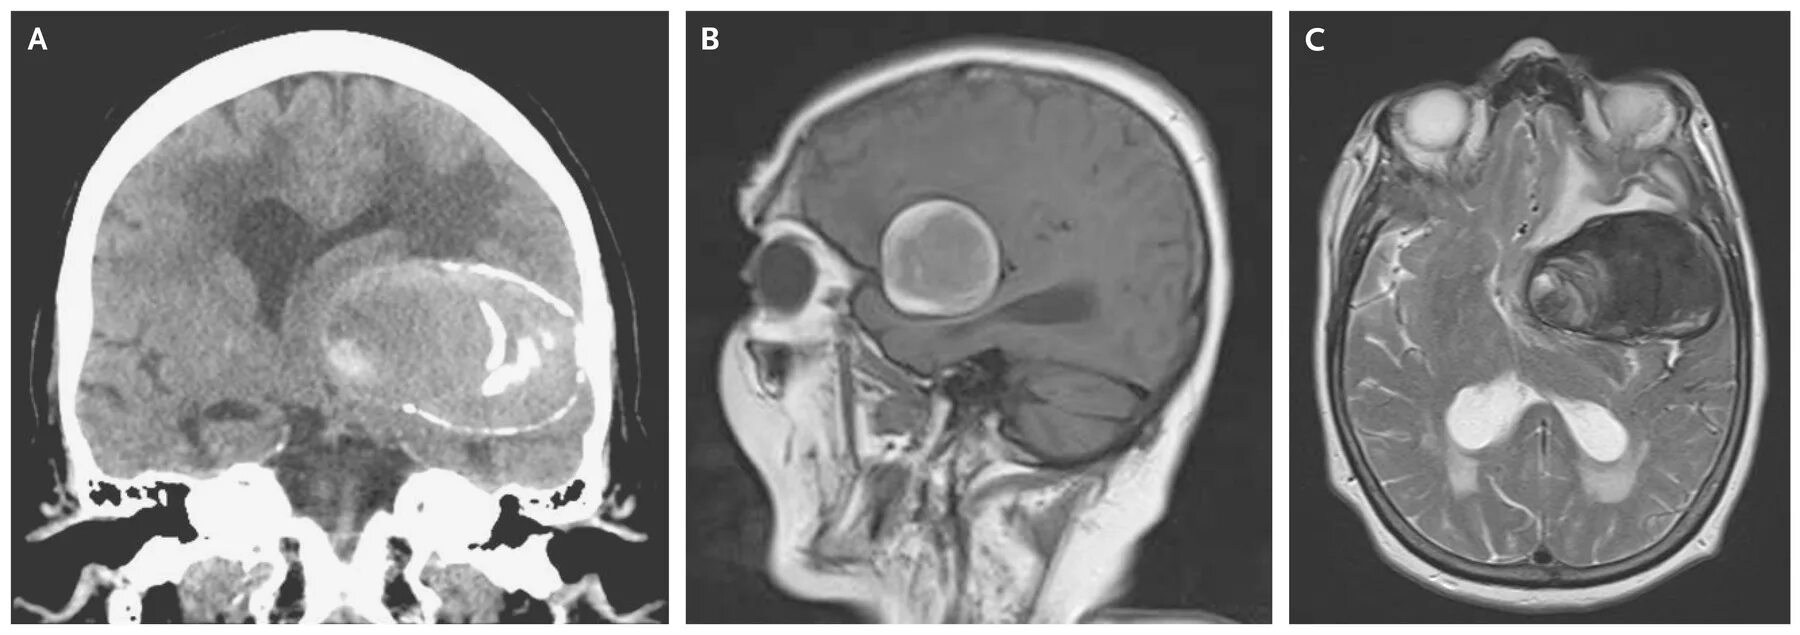

Аневризма головного мозга на кт